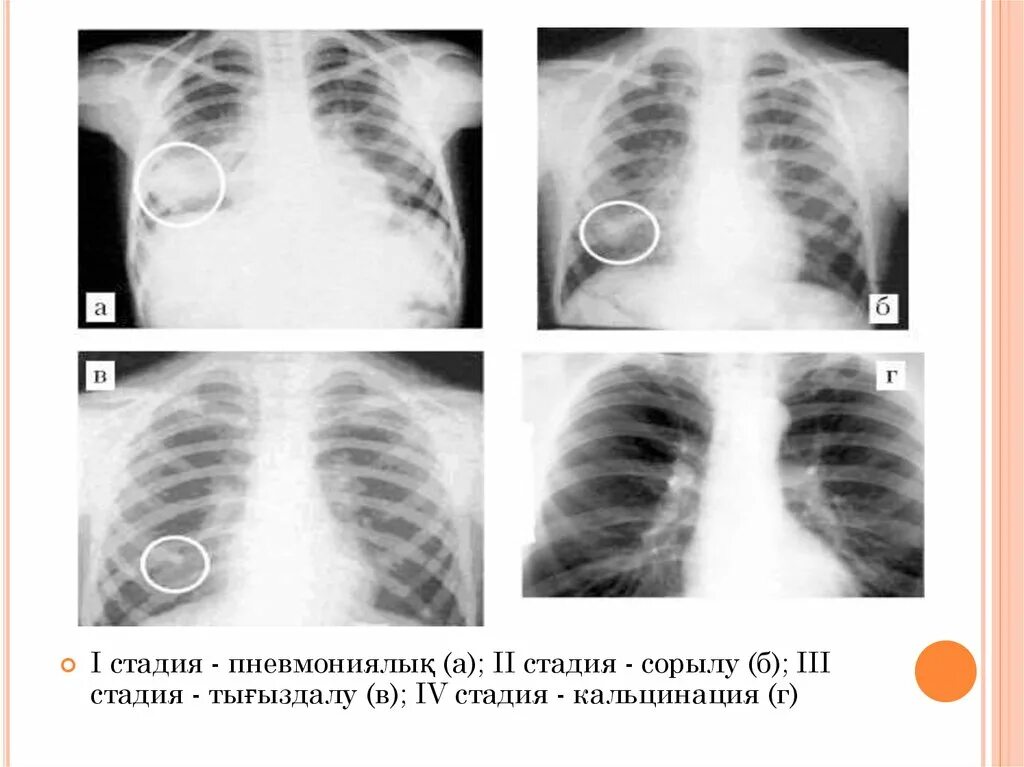

Бронхоаденит это